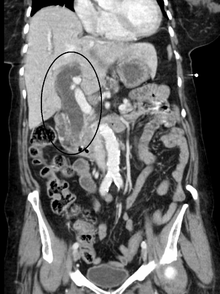

Post-hepatic jaundice, also called obstructive jaundice, is caused by an interruption to the drainage of bile containing conjugated bilirubin in the biliary system. The most common causes are gallstones in the common bile duct, and pancreatic cancer in the head of the pancreas. Also, a group of parasites known as "liver flukes" can live in the common bile duct, causing obstructive jaundice. Other causes include strictures of the common bile duct, biliary atresia, cholangiocarcinoma, pancreatitis, cholestasis of pregnancy, and pancreatic pseudocysts. A rare cause of obstructive jaundice is Mirizzi's syndrome.